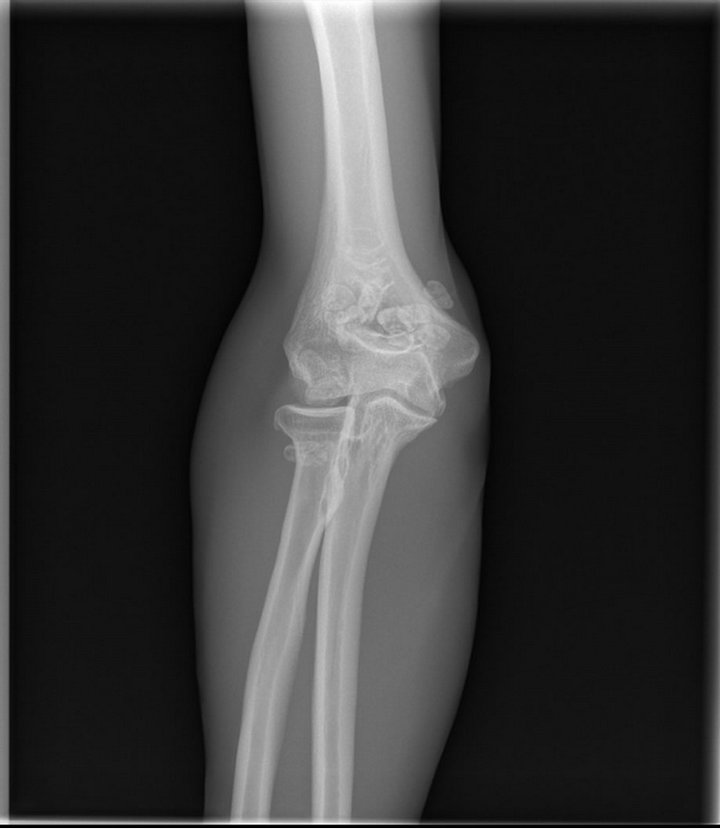

Synovial chondromatosis of the elbow joint Image Synovial Osteochondromatosis Elbow synovial chondromatosis is a proliferative disease of the synovium associated with cartilage metaplasia that results in multiple intra. primary synovial chondromatosis (psc) is a rare and benign disorder of the mucosal membrane in joints, bursae, and tendon sheaths. synovial chondromatosis (sc) is a benign uncommon condition of the synovial membrane of joints, tendon sheaths, and bursae that. Synovial Osteochondromatosis Elbow.

x ray of a Synovial chondromatosis elbow Stock Photo Adobe Stock Synovial Osteochondromatosis Elbow synovial chondromatosis most often occurs in the knee, followed by the hip, elbow, and shoulder. the purpose of this technical note is to describe the details of arthroscopic synovectomy and removal of loose bodies for management of. synovial chondromatosis is a proliferative disease of the synovium associated with cartilage metaplasia that results in multiple intra. primary. Synovial Osteochondromatosis Elbow.

Synovial osteochondromatosis Image Synovial Osteochondromatosis Elbow primary synovial chondromatosis (psc) is a rare and benign disorder of the mucosal membrane in joints, bursae, and tendon sheaths. synovial chondromatosis (osteochondromatosis or synovial chondrometaplasia) also known as reichel. synovial chondromatosis is a proliferative disease of the synovium associated with cartilage metaplasia that results in multiple intra. In most cases, only one joint in the body. Synovial Osteochondromatosis Elbow.

Synovial osteochondromatosis Radiology Case Synovial Osteochondromatosis Elbow synovial chondromatosis is a proliferative disease of the synovium associated with cartilage metaplasia that results in multiple intra. the purpose of this technical note is to describe the details of arthroscopic synovectomy and removal of loose bodies for management of. synovial chondromatosis most often occurs in the knee, followed by the hip, elbow, and shoulder. synovial. Synovial Osteochondromatosis Elbow.